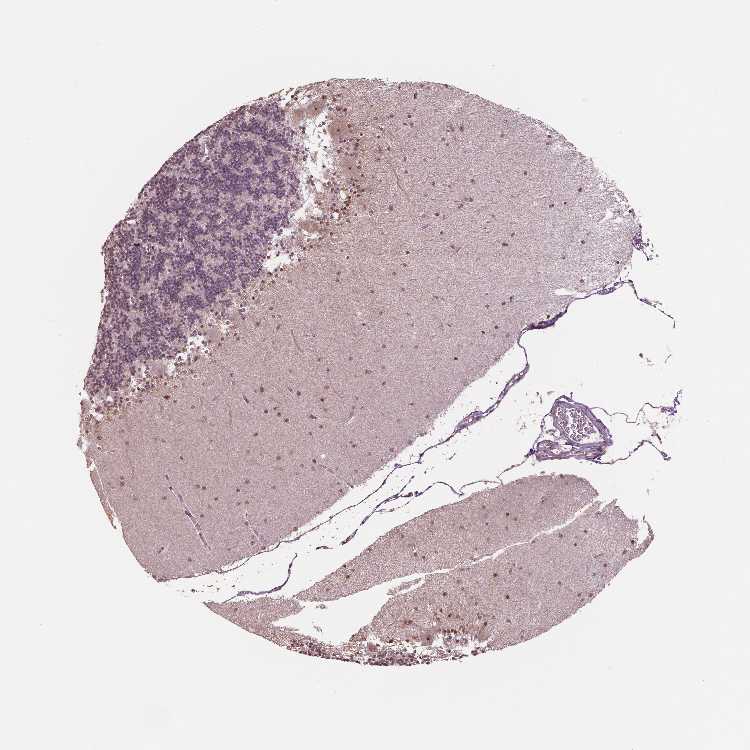

BRAIN CEREBELLUM Show tissue menu

CEREBELLUM - Expression summary

CEREBELLUM - Antibody stainingi

Antibody staining in the annotated cell types in the current human tissue is reported as not detected, low, medium, or high, based on conventional immunohistochemistry profiling in selected tissues. This score is based on the combination of the staining intensity and fraction of stained cells.

Each image is clickable and will lead to virtual microscopy that enables deeper exploration of all samples and also displays staining intensity scores, fraction scores and subcellular localization as well as patient and tissue information for each sample.

Antibody HPA054505Antibody HPA057799Antibody CAB015226

Purkinje cells LowNot detectedMedium

Cells in granular layer LowLowMedium

Cells in molecular layer LowLowMedium